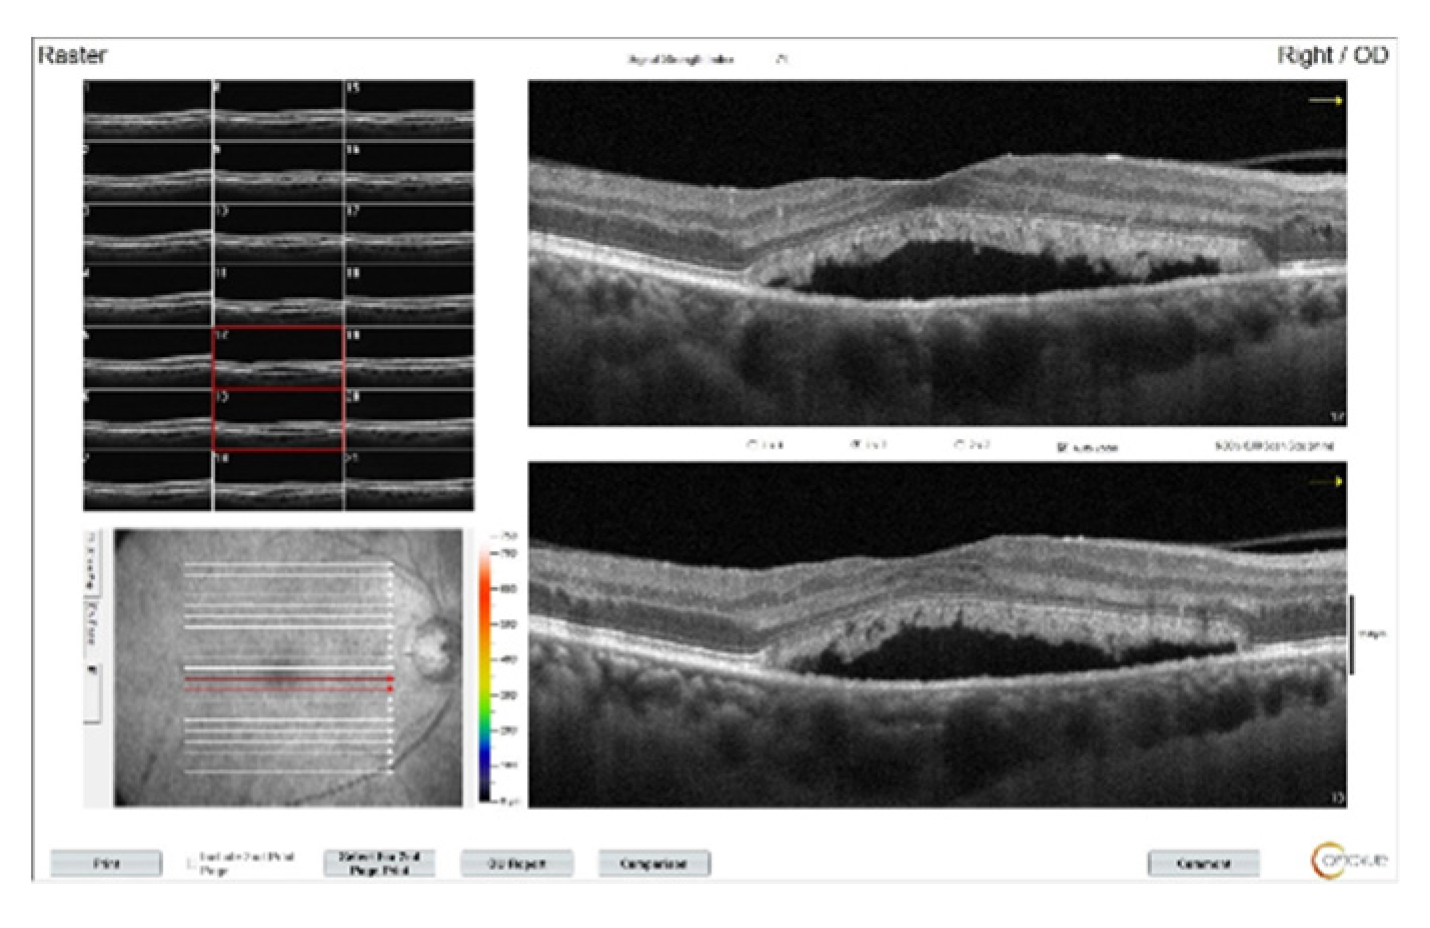

In his examination after 3 intravitreal bevacizumab injections to both eyes, BCVA decreased to 20/100 in the right eye and to 20/60 in the left eye, and OCT images showed a decrease in intraretinal fluid, but there was no regression in SRDs (Figure 3). Continuining panretinal photocoagulation was scheduled due to the capillary ischemia in the fundus fluorecein angiography (FFA) (Figure 4). However, since there was no apparent leakage in the macula on FFA, increased subretinal deposits were noted on OCT (Figure 3), and the patient’s complaints of weakness and fatigue, an internal medicine consultation was requested. Laboratory tests showed hemoglobulin 6.8 g/dl (normal range:13.1-17.2 g/dl), albumin 23 g/l (normal range:35-52 g/dl), erythrocyte sedimentation rate 140 mm/h (normal value:< 15 mm/h), C-reactive protein 14.9 mg/l (normal value:<6 mg/l) and hemoglobin A1c 8.1% (normal range:3.5- 5.7 %) in the blood, and there was +3 proteinuria in the urine. Lymphadenopathy was detected in the left inguinal region. Abdominal computerized tomography was interpreted by radiologist as “Lytic bone lesions in the left iliac wing and right acetebulum, partial involvement in the L3 vertebra and near-total involvement in the L4 vertebra. Metastasis? Multiple myeloma?”. The patient was diagnosed with multiple myeloma (MM) with protein electrophoresis and hematologic examination. The patient was subsequently started on systemic chemotherapy for MM and no additional injections were administered for macular edema. With the beginning of treatment, the macular subretinal fluid gradually decreased and disappeared bilaterally. At the 1st year follow-up, BCVA was 20/80 on the right eye and 20/100 on the left. OCT images of the patient during follow-up can be seen in Figure 5.

Figure 3. OCT images of the right eye after three doses of intravitreal bevacizumab. Intraretinal edema has resolved, but subretinal fluid persists and subretinal deposits are becoming more apparent.